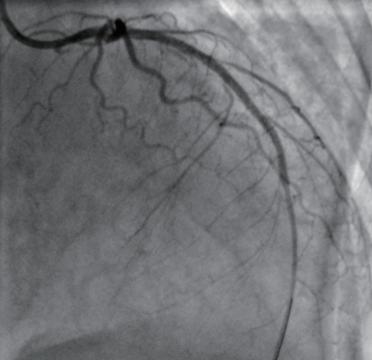

(3)指引导管到位后,根据患者的体重使用肝素钠,肝素钠总量为每千克体重100U。然后经指引导管送冠状动脉旋磨导丝通过病变部位到达血管腔远端(图1-3-2),沿旋磨导丝以低转速方式送旋磨头至病变前端,开启旋磨液开关以保证旋磨液持续加压灌注,转换旋磨转速为高速,操纵推进器推送旋磨头至斑块处,以啄木鸟式慢进快出进行斑块的旋磨。

图1-3-2 旋磨头通过冠状动脉狭窄处的造影